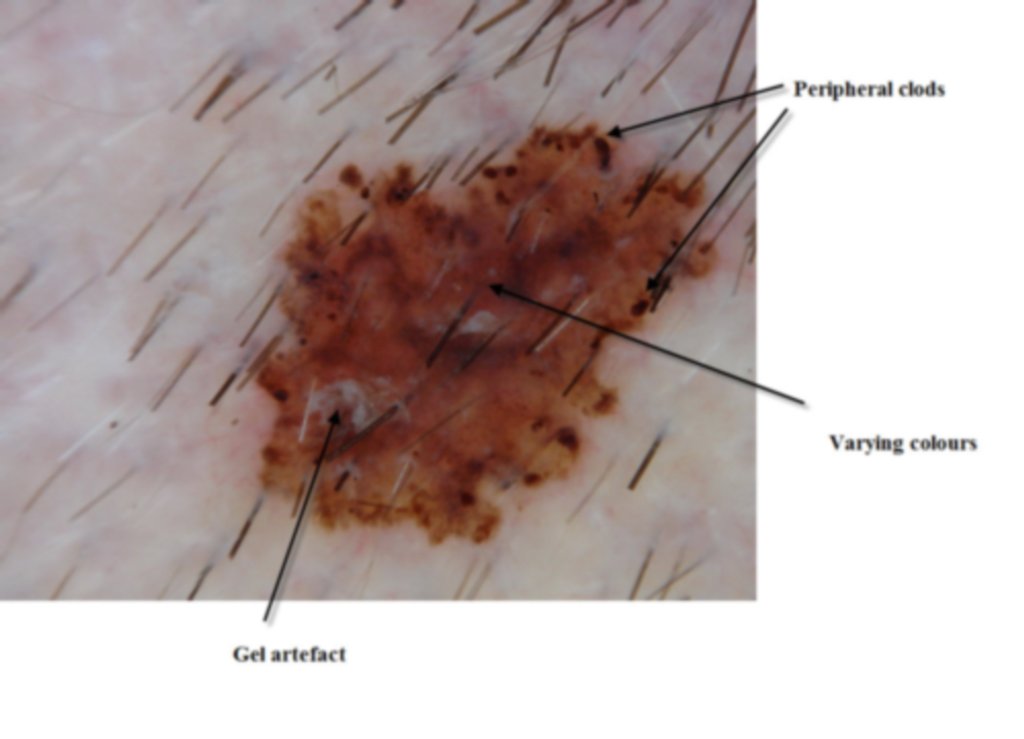

This lesion was noted fotuitously when the patient was having another procedure done on his back. Dermatoscopically it shows peripheral clods of varying sizes, multiple colours and on the enlarged dermatoscopic view some diffuse fine grey dots. It was an invasive melanoma Level 2 , 0.4mm in depth . The histology shows an unusual feature of acantholysis of the tumour nests.